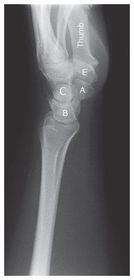

A. trapezoid B.. trapezium C. capitate D. scaphoid E. hamulus F. hamate G. triquetrium H. pisiform I. lunate J. ulna

A. scaphoid B. lunate C. capitate E. trapezium